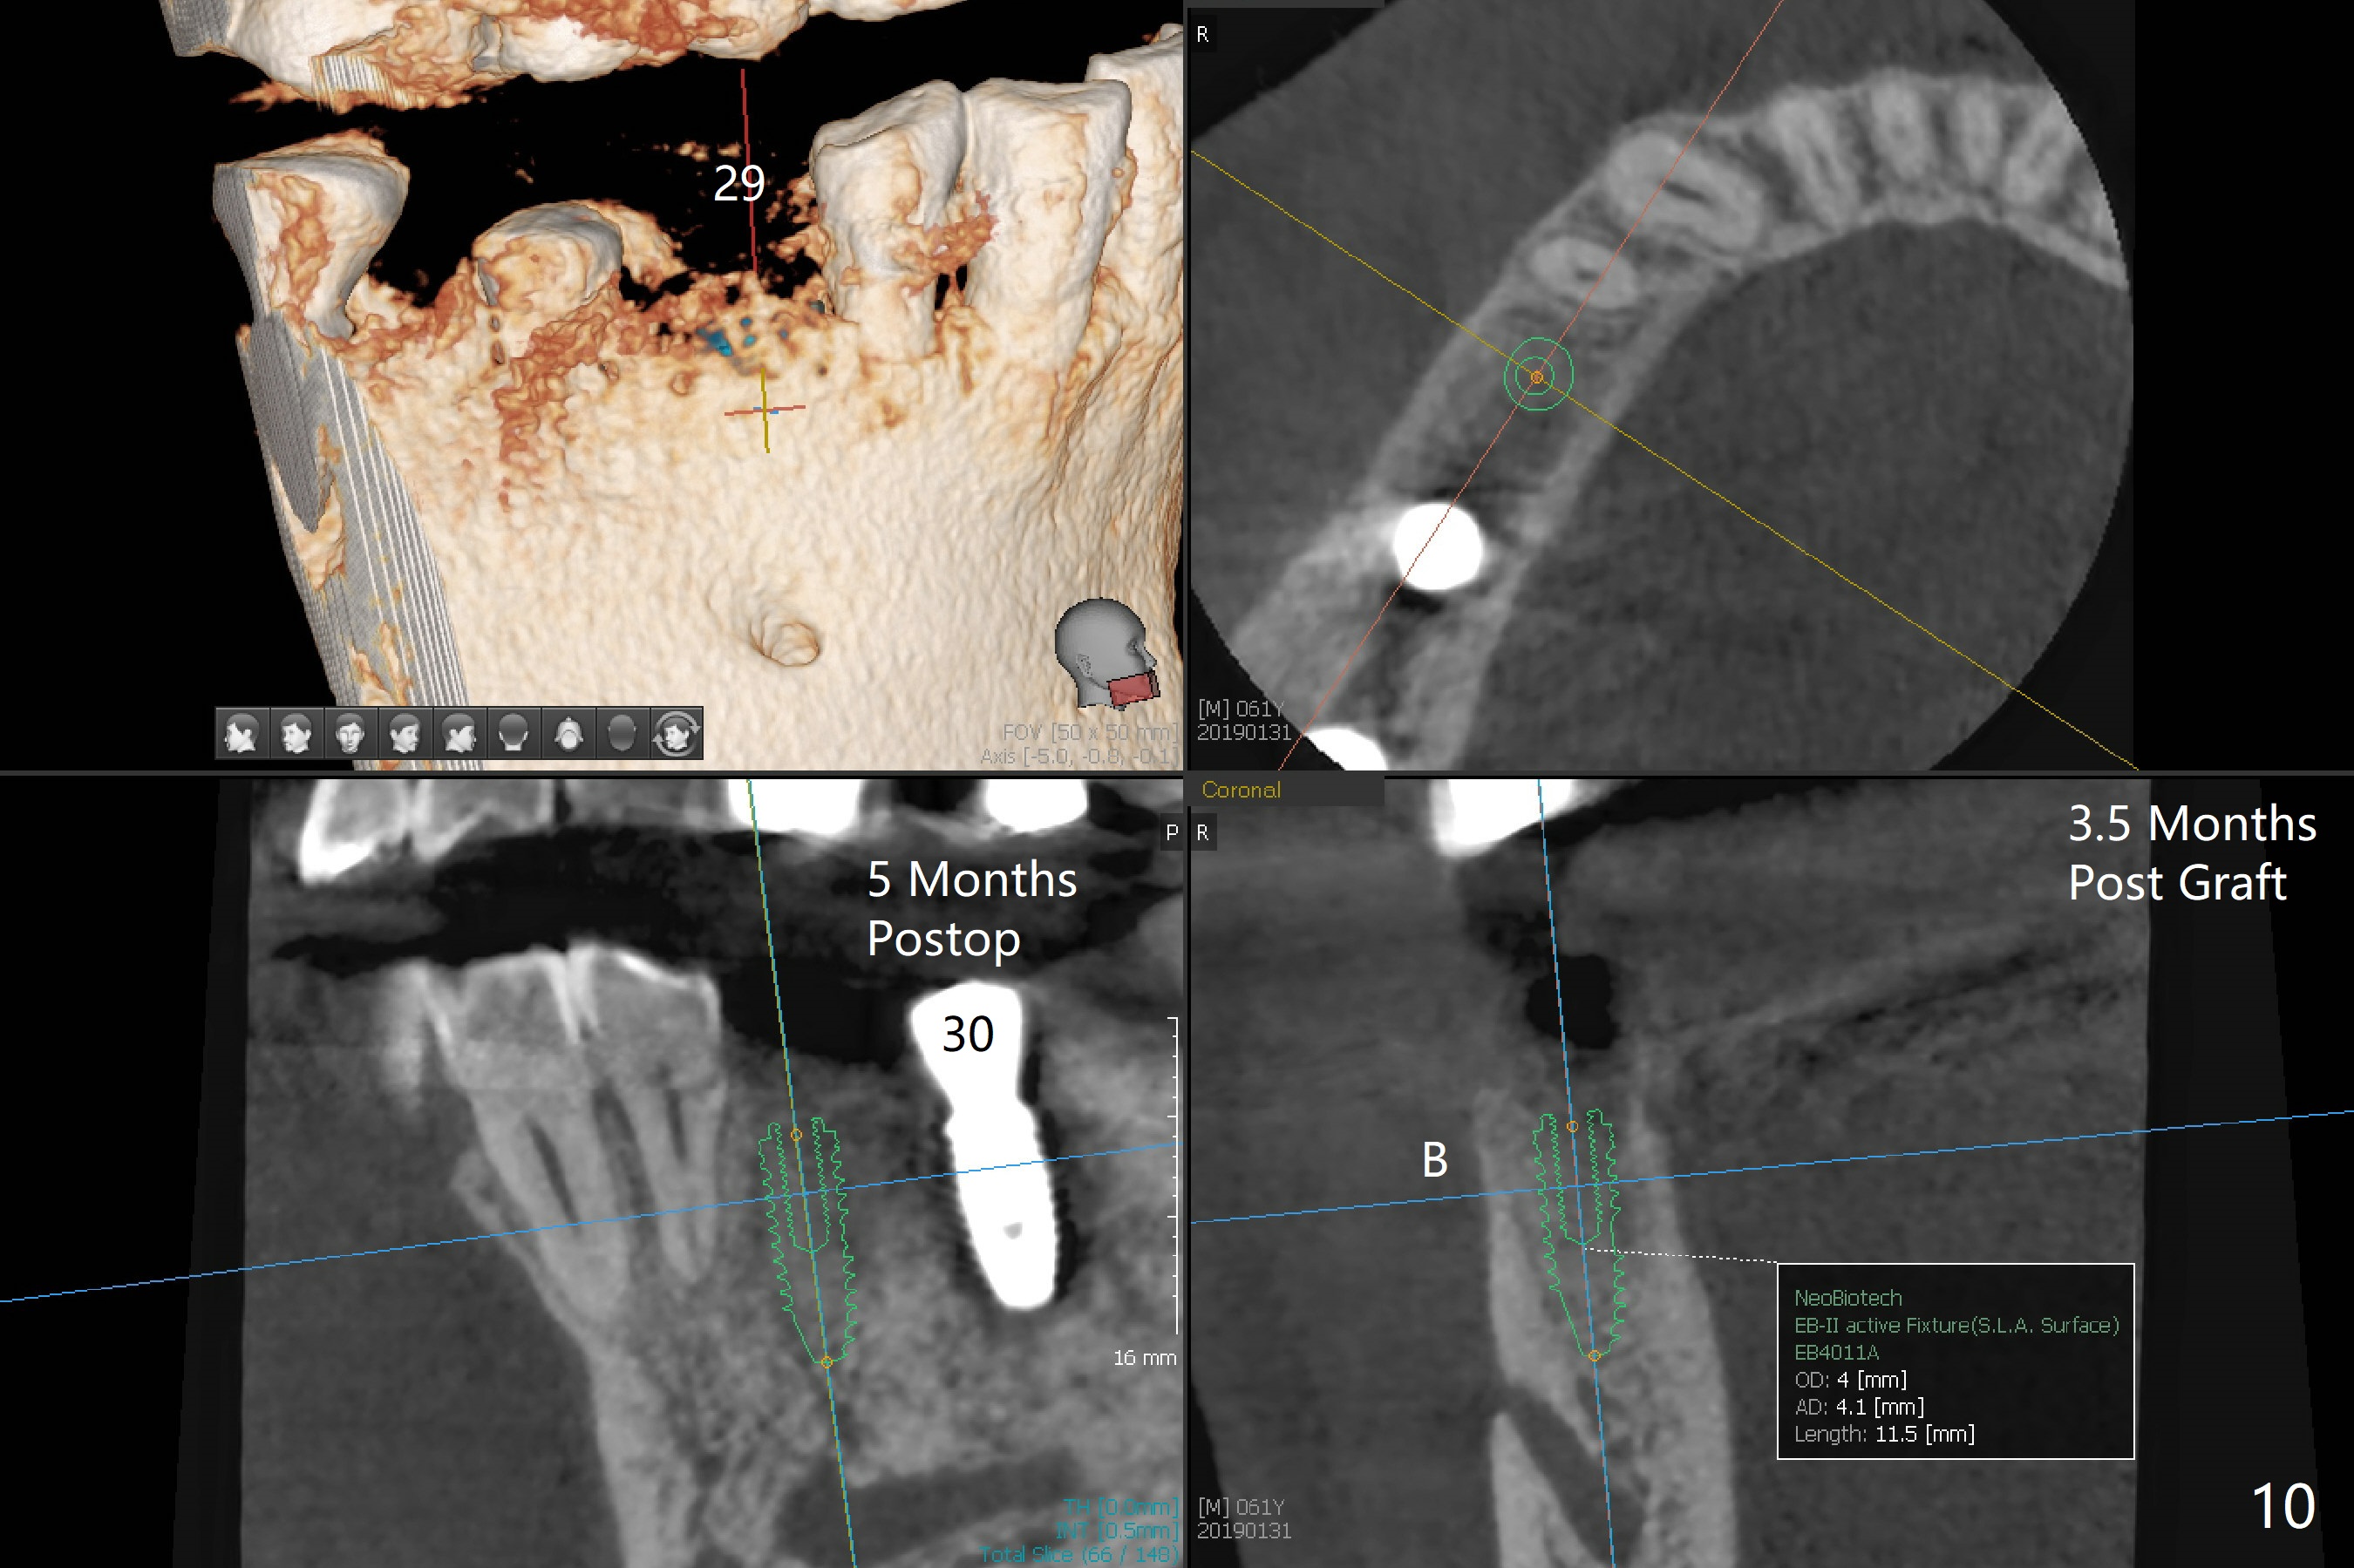

An endodontist refuses RCT retreatment at #29 because of short root. The patient is hesitant about apicoectomy. After discussion of advantages and disadvantages of the latter vs. extraction and implant, the patient chooses the extraction. The latter turns out to be smooth with socket preservation (Fig.4, 5 *). Immediately postop PA shows bone loss at #30 and minor degree around the apex of #31 implant (Fig.4 <), which is probably related with hard bone and bone necrosis due to heat. The headache disappears 1 week postop (Fig.6). The patient does not take pain medication. There is no percussion at #30 (Fig.7). The healing abutments are stable. The patient will return for #30 and 31 restoration nearly 4 months postop and 2 months post #29 extraction. Splinted provisional will be placed if the implants heal. Impression will be taken for #29 guide 4 months post socket preservation. After re-analysis of CT, it appears that a long implant (4x15 mm to gain 3.9 mm fixation in the native bone) will be placed free hand at #29 four months post socket preservation (Fig.8). The bone loss around the implants at #30 and 31 persists 3.5 month postop, while the socket heals at #29 2 months post socket preservation (Fig.9). When the healing abutments with plaque are removed, there is granulation tissue around the gingival cuffs with tenderness. The abutments with heavy plaque (similar to that in Fig.7) are reloaded after cleaning with OHI. The patient returns for CT and impression for #29 guide 3.5 months post socket preservation and 5 months post implant placement. While bone necrosis remains severe at #30, the socket at #29 seems to have healed (Fig.10). Oral hygiene improves with healthy gingiva, but there is tenderness when a cementation abutment is placed. Implant design before and after extraction at #29 (Fig.11,12). Gingiva becomes inflamed at #31 when a splinted provisional is being worn to intrude the opposing supraerupted teeth; bone resorption remains severe in the previous distal socket and the mesial necrotic area (Fig.13 S, N). Pain persists after placement of a healing screw. In spite of severe bone loss, especially distal, the buccal plate is present. When the implant at #31 is removed, there is a large defect with granulation tissue apicobuccal to the buccal plate, corresponding to the presumptive mesial necrotic area (Fig.13,14 N). Vanilla graft mixed with PRF ("sticky bone" too rigid) is placed in the defect, followed by a piece of PRF membrane and 6-month one. The pain appears not to reduce and nearly 1 month later transfers to the buccal of #30.